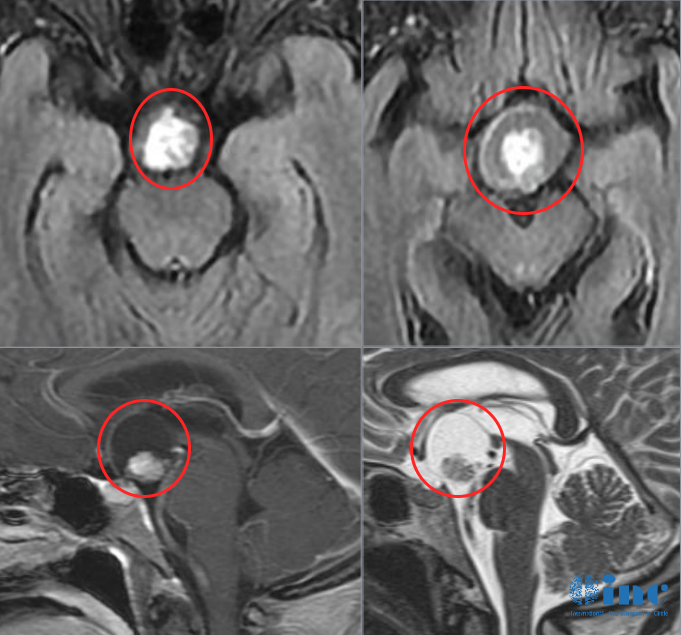

▲术前术后影像对比,红色为术前肿瘤位置,绿色为术后切除效果